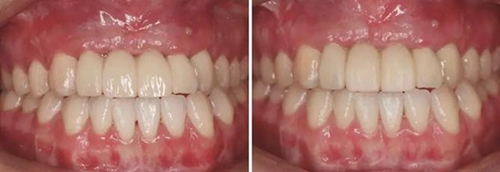

(4)2015年3月—2015年12月:早期修復(fù)伴軟組織誘導(dǎo)成形對(duì)患者制取開窗印模后,使用橋用金屬臨時(shí)基臺(tái),制作聚甲基丙烯酸甲酯(PMMA,登士柏公司,德國)經(jīng)CAD/CAM切削的臨時(shí)修復(fù)橋體,戴入臨時(shí)修復(fù)體對(duì)牙齦軟組織進(jìn)行誘導(dǎo)成形,采用動(dòng)態(tài)加壓技術(shù),最初緩慢戴入臨時(shí)修復(fù)體,撐開牙齦軟組織袖口,擠壓粘膜,粘膜受到擠壓后缺血變白,10min內(nèi)可恢復(fù)為粉紅色。臨時(shí)修復(fù)體為縱向螺絲固位,便于拆卸調(diào)改形態(tài),囑患者勿用臨時(shí)修復(fù)體咬物,注意口腔衛(wèi)生,用牙線或沖牙器等將種植體周圍清潔干凈,每月進(jìn)行復(fù)查,不斷調(diào)改臨時(shí)冠的穿齦形態(tài),讓出軟組織生長空間,直至誘導(dǎo)牙齦形成類似于天然牙的穿齦袖口形態(tài)。其中在早期修復(fù)3月時(shí),通過打開修復(fù)體間的三角間隙,以讓出齦乳頭生長的空間;在早期修復(fù)7月時(shí)對(duì)22位點(diǎn)唇側(cè)牙齦根方的軟組織增生物進(jìn)行刮除并縫合,同時(shí)將修復(fù)體的橋體部位調(diào)磨成卵圓形的蓋嵴部并高度拋光,以獲得良好的橋體部軟組織形態(tài),形成健康、連續(xù)且協(xié)調(diào)的軟組織輪廓。

圖19 早期修復(fù)1月 圖20 早期修復(fù)2月

圖21 早期修復(fù)3月 圖22 早期修復(fù)3月打開三角間隙

圖23 早期修復(fù)4月 圖24 早期修復(fù)7月切除軟組織增生后

圖25 早期修復(fù)7月調(diào)改橋體部形態(tài)為卵圓形并高度拋光 圖26 早期修復(fù)8月

圖27 早期修復(fù)8月調(diào)改后 圖28 早期修復(fù)10月